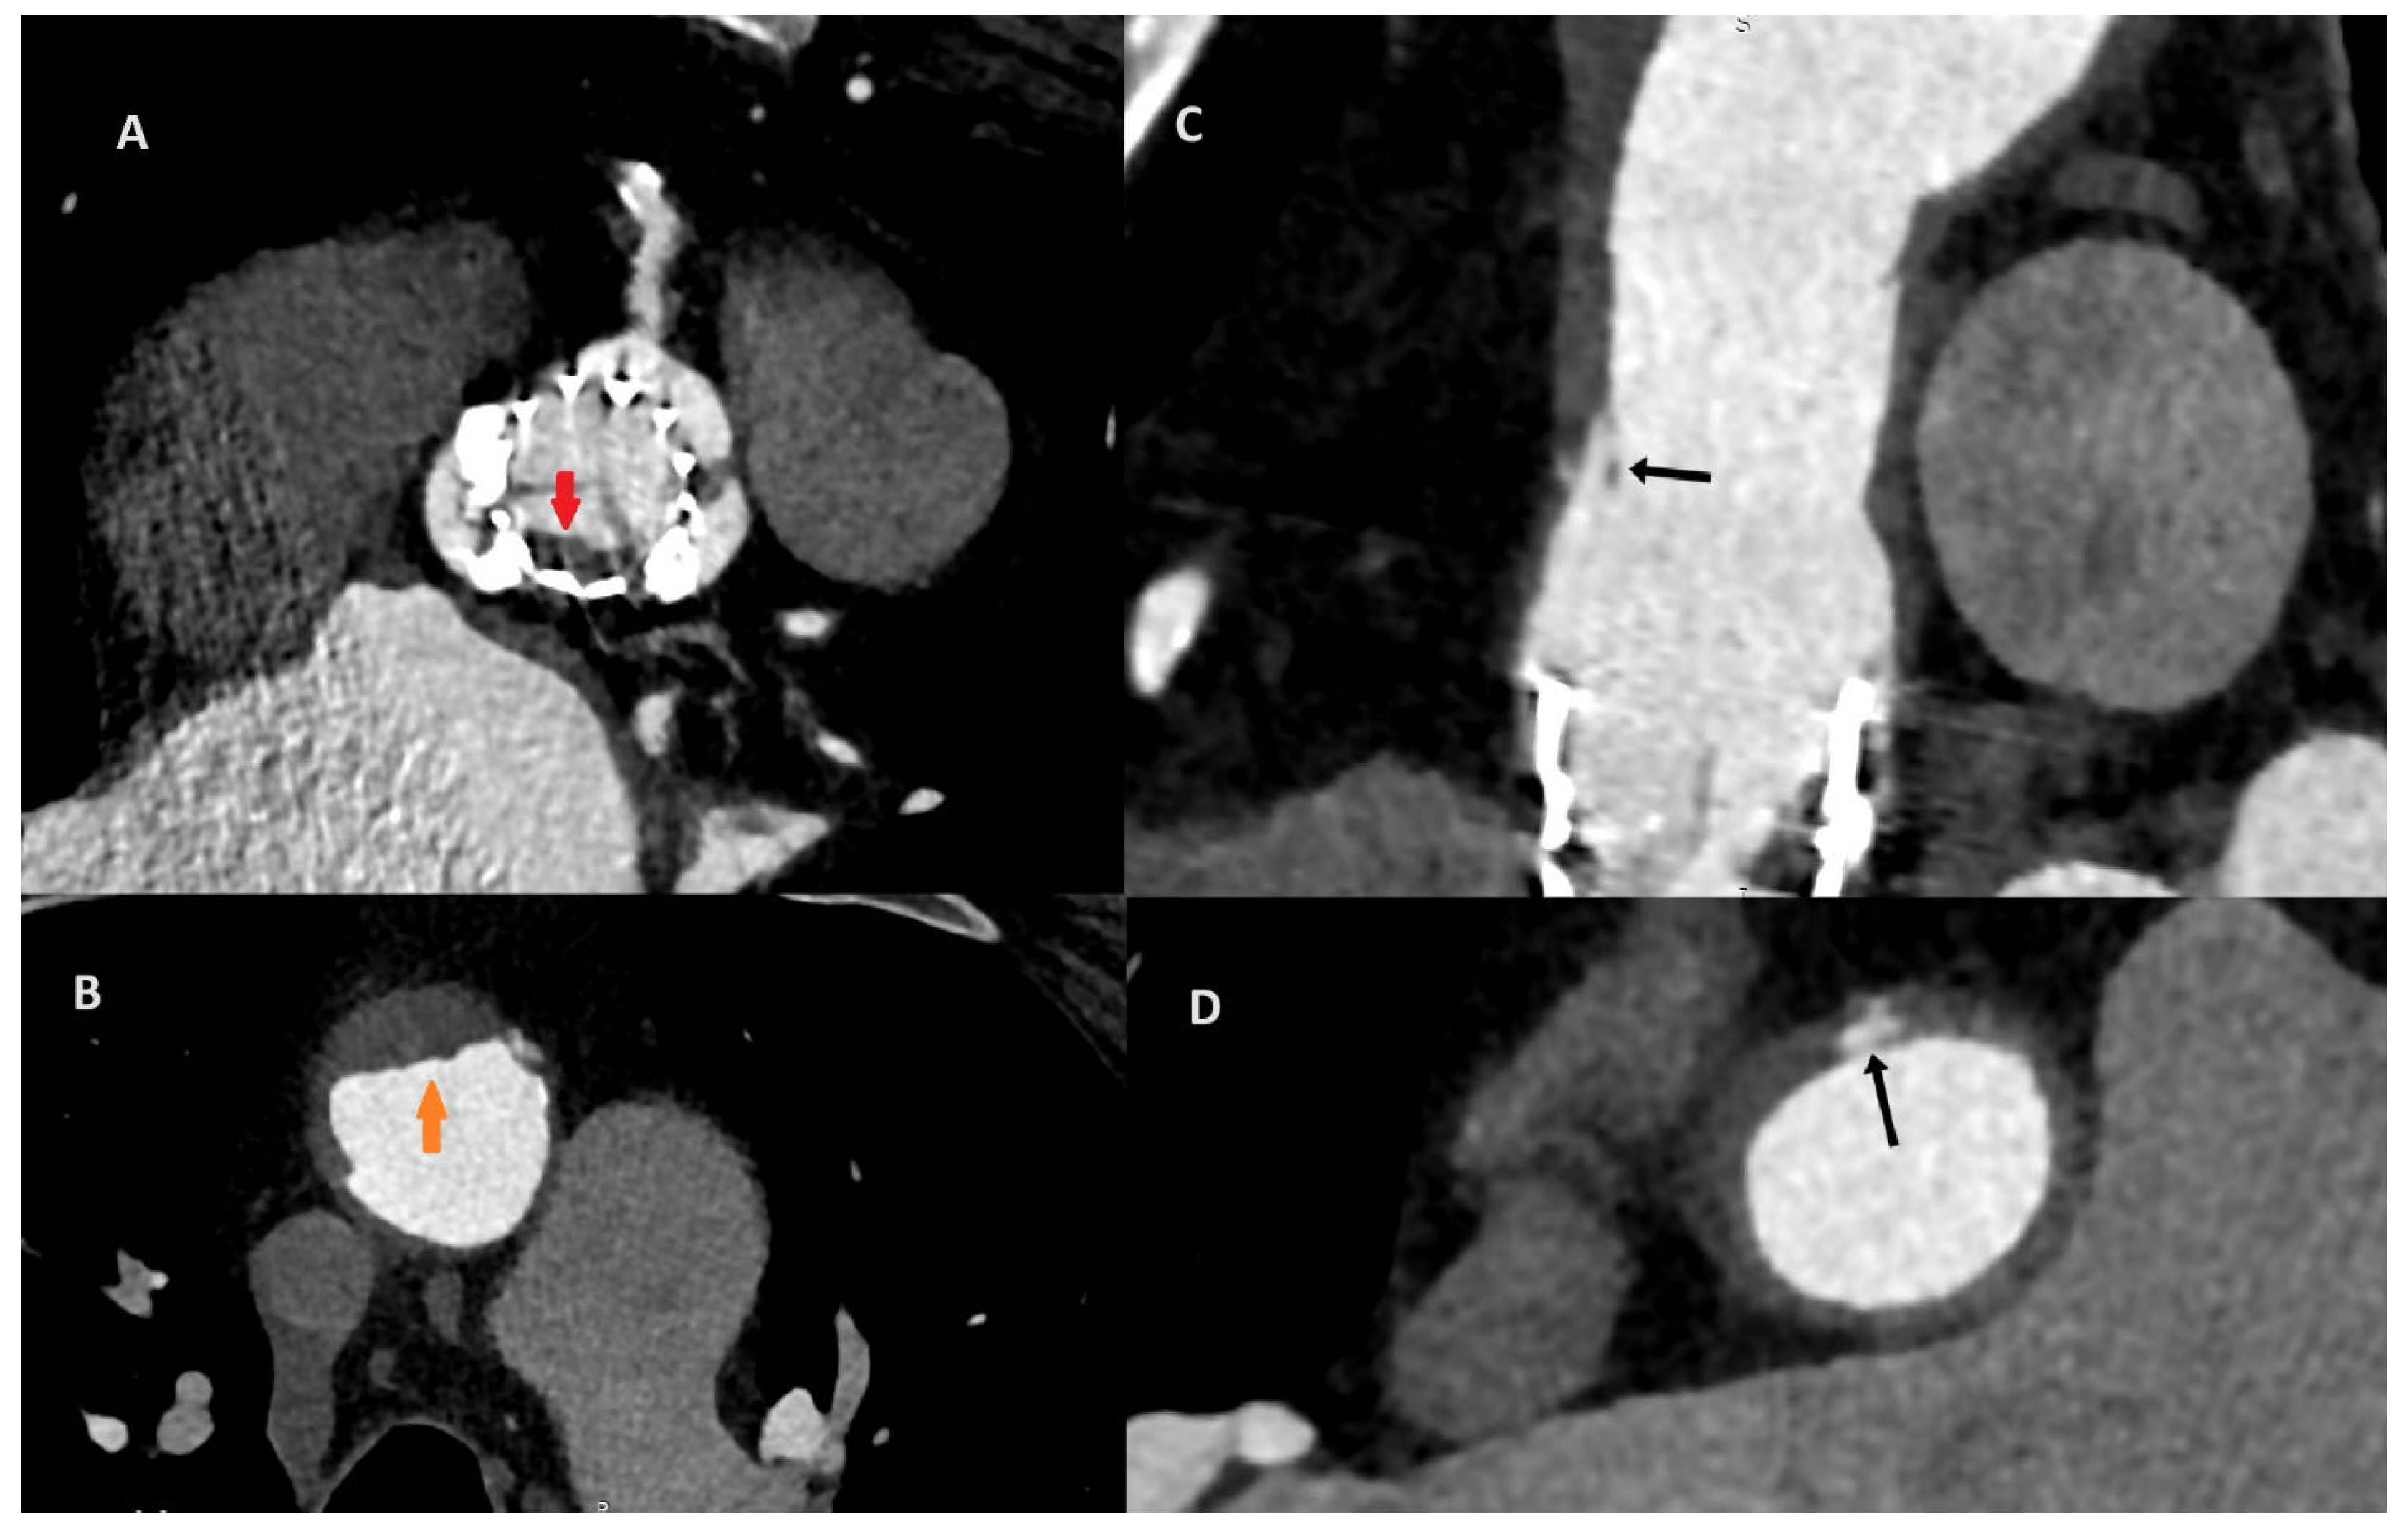

After the consultation with the cardiac radiologist, the third ECG-gated cardiac CT was performed on the eighth day after the initial CT to access both the aorta and coronary arteries. To increase the quality of the image, an additional beta-blocker and nitroglycerin were administered before examination. The CT revealed aortic valve prosthesis thrombosis (A; red arrow) and a reduction in aortic thrombosis (B; orange arrow). The previous thrombus site was localized to originate within the ascending aorta graft, which was covered by soft tissue that resembled an ulcer. The probable dissection of the neointima along the prosthesis was the suspected cause of the initial aortic thrombosis (C,D; black arrow).